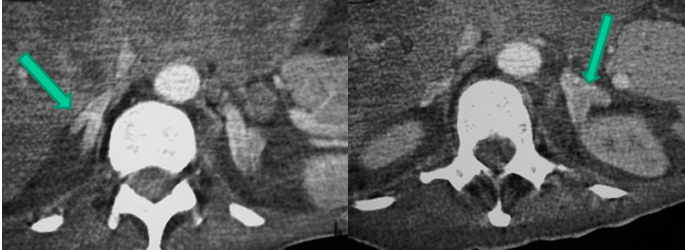

-”string of beads” characteristic of medial fibromuscular dysplasia

-renal artery stenosis

renovascular hypertension

-diagnosis: renin levels can be high but normal levels do not rule out renal artery stenosis

-imaging studies: sonography with duplex doppler, magnetic resonance angiography, CT angiography, angiography

-due to fibromuscular dysplasia in young individuals- treat with angioplasty

-due to atherosclerotic disease in older individuals with CV risk factors: suspect with pre-existing peripheral vascular disease or long history of smoking, recurrent flash pulmonary edema, treatment with angioplasty + stent placement